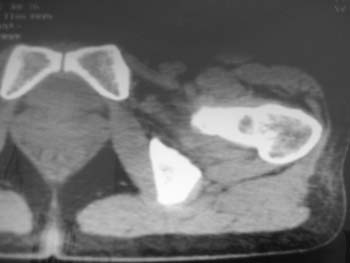

以下是引用358450m在2008-8-12 12:12:00的发言:[br]骨囊肿

以下是引用yangyudong333在2008-8-12 14:30:00的发言:[br]考虑退京变所致关节面下骨质囊变

以下是引用随光逐影在2008-8-12 20:40:00的发言:[br]考虑邻关节骨囊肿或骨内腱鞘囊肿。